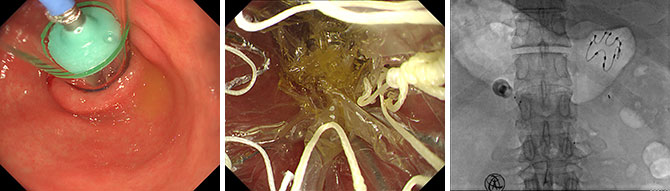

省医首例经胃镜胃转流支架置入术

通过胃镜在十二指肠及空肠上段置入一个60 cm的膜状套管隔离食糜与肠黏膜接触,干预食物的消化吸收,从而达到不开刀、不节食也能治疗肥胖及肥胖相关合并症的目的。支架置入期为3个月,到期需来院取出。

胃转流支架示意图